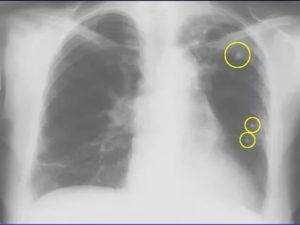

Что можно увидеть на снимке курильщика

У курильщиков со стажем обычно развивается хроническая обструктивная болезнь лёгких. При этом лёгочный рисунок будет усилен, особенно в нижних отделах. Компенсаторно встречаются участки просветления – эмфизема.

У курильщиков увеличивается размер между рёбрами, диафрагма постепенно опускается, а купола – сглаживаются. Угол между ребром и диафрагмой постепенно превращается из острого в прямой. Как результат, возникает гипоксия, или дефицит вентиляции лёгких. При этом орган не может нормально выполнять свою функцию.

Что не описывает расшифровка рентгеновских снимков лёгких

рентгенограмма и флюорограмма курильщика: в чем отличие от нормы

Курение сигарет наносит непоправимый вред дыхательной системе человеческого организма, что особенно сильно проявляется при многолетнем стаже, вязаного с этой вредной привычкой. Рентген легких курильщика и здорового человека отличаются.

Для рентгенологических снимков курящего в день по одной пачке сигарет характерно присутствие полостных образований в бронхах (бронхоэктазов) и сгущение легочного рисунка. Прикорневые области также претерпевают изменения, что связано с их деформацией, размытостью и плохим выделением их признаков по снимку, дополнительными тенями.

Флюорография легких курильщика показывает картину легких с множественным количеством пор, образованных изменениями воспалительного характера и бронхиальными дефектами. Это связано с гибелью клеток дыхательного древа и дисфункцией альвеол, которые способствуют доставке кислорода в ткани.

Вышеуказанные симптомы формируют дыхательную недостаточность. На снимках выражаются просветлениями полей легких, означающих повышенную воздушность. Постепенно из нижней части этот признак перемещается вверх легочных полей.